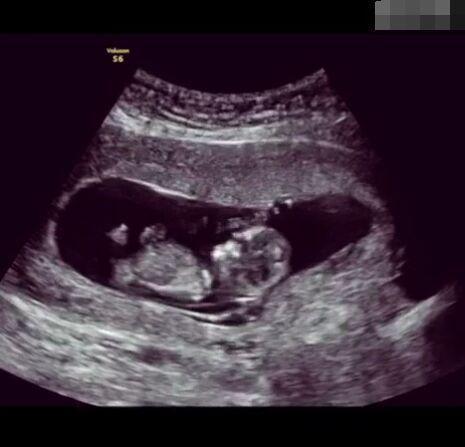

懷孕后,寶寶的性別一直是全家人的重點(diǎn)關(guān)注對象。而男女性別的差異,在基因?qū)用骟w現(xiàn)在第二十三對染色體上,如果是XY則是男孩,XX則是女孩,這都是由那枚與卵子結(jié)合的精子來決定。

圖片8.png

那些做了B超檢查確定胎兒男女,生下來后發(fā)現(xiàn)不對的,多半是因?yàn)樵贐超檢查時寶寶太調(diào)皮,以致影響了檢查準(zhǔn)確性。就比如說,有的女寶寶在媽媽肚子里玩自己的臍帶,把臍帶夾到了兩腿中間,B超就有一定幾率拍出來好像是男寶寶的特征,導(dǎo)致被誤認(rèn)為是男孩子。還有些男寶寶過分害羞,在做B超時雙腿緊緊并攏,醫(yī)生也很難判斷男女,只好大致猜測是女孩,就又造成了誤會。因此,B超亦不是萬能的。